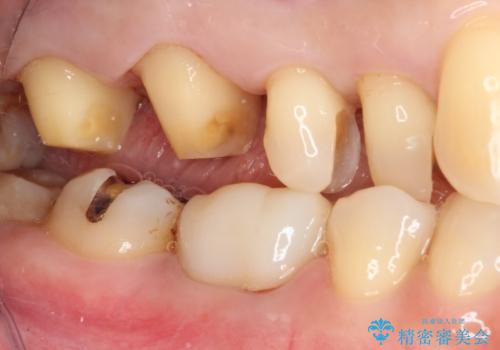

- 奥歯の銀歯をセラミックの白い歯にして、しみる症状も改善したいとのことで来院された患者様です。

知覚過敏の症状が強い歯と、銀歯の範囲や銀歯の下のむし歯が大きい歯は、インレー修復では対応が難しいためオールセラミッククラウンで、インレー修復で対応が可能な歯ではセラミックインレーにて修復することとしました。